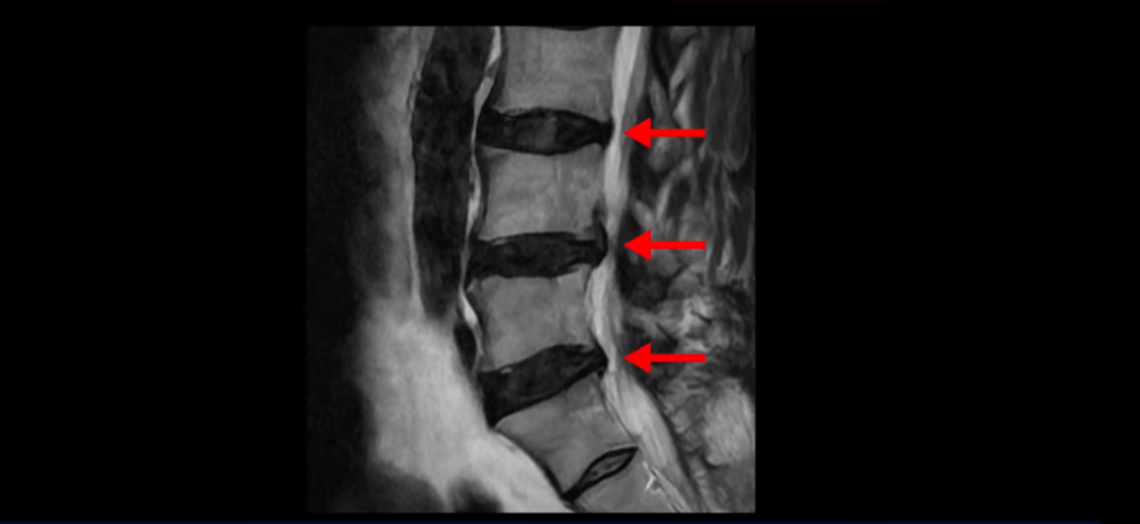

이분 MRI를 보면 허리 세 마디 정도의 퇴행성 디스크가 있고

4번 5번 마디에는 중심성 협착이 있습니다.

후관절과 황색인대가 두꺼워져 있어서 척추관이 좁아져 있습니다.

하지만 이분의 갑작스러운 통증을 일으키는 원인은 4번 5번에 발생한 디스크 파열입니다.

이분은 왼쪽 무릎 아래로 본인 표현으로는 다리를 잘라 버리고 싶다고 할 정도의 심한 통증이 있는데 보통 이런 표현은 디스크 파열이 발생했을 때 많이 사용하는 표현입니다. 이분 4번 5번 디스크를 자세히 보면 왼쪽으로 파열되어 밀려 올라간 디스크 수핵을 볼 수 있습니다.